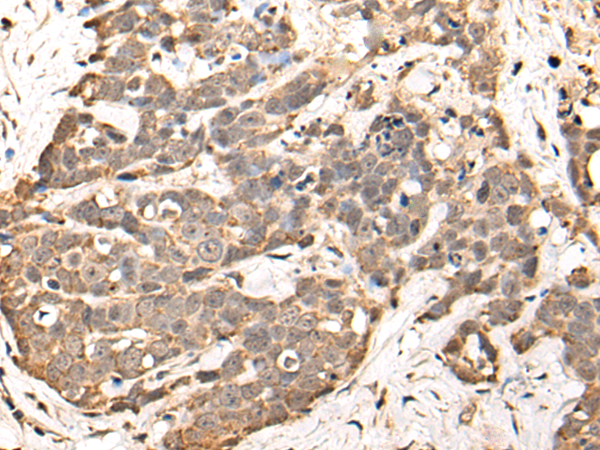

分类: 科研抗体货号: P02304别名: ALFY; ZFYVE25应用: IHC反应种属: Human, Mouse